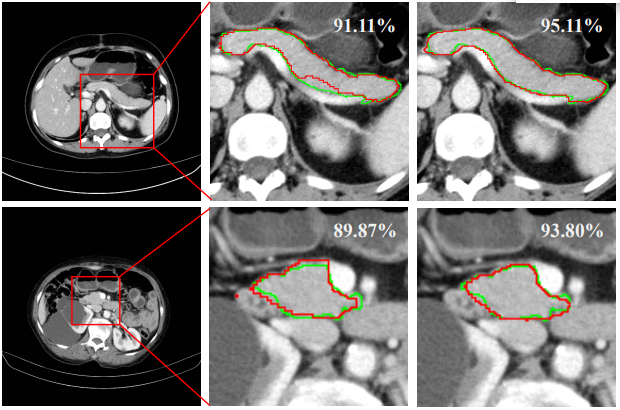

The complementation of arterial and venous phases visual information of CTs can help better distinguish the pancreas from its surrounding structures. However, the exploration of cross-phase contextual information is still under research in computeraided pancreas segmentation. This paper presents M 3 Net, a framework that integrates multi-scale multi-view information for multi-phase pancreas segmentation. The core of M 3 Net is built upon a dual-path network in which individual branches are set up for two phases. Cross-phase interactive connections bridging the two branches are introduced to interleave and integrate dual-phase complementary visual information. Besides, we further devise two types of non-local attention modules to enhance the high-level feature representation across phases. First, we design a location attention module to generate cross-phase reliable feature correlations to suppress the misalignment regions. Second, the depth-wise attention module is used to capture the channel dependencies and then strengthen feature representations. The experiment data consists of 224 internal CTs (106 normal and 118 abnormal) with 1mm slice thickness, and 66 external CTs (29 normal and 37 abnormal) with 5mm slice thickness. We achieve new state-of-the-art performance with average DSC of 91.19% on internal data, and promising result with average DSC of 86.34% on external data.